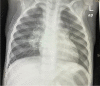

Tuberculosis (TB) remains one of the major public health threats worldwide, despite improved diagnostic and therapeutic methods. Tuberculosis is one of the main causes of infectious disease in the chest and is associated with substantial morbidity and mortality in paediatric populations, particularly in low- and middle-income countries. Due to the difficulty in obtaining microbiological confirmation of pulmonary TB in children, diagnosis often relies on a combination of clinical and radiological findings. The early diagnosis of central nervous system TB is challenging with presumptive diagnosis heavily reliant on imaging. Brain infection can present as a diffuse exudative basal leptomeningitis or as localised disease (tuberculoma, abscess, cerebritis). Spinal TB may present as radiculomyelitis, spinal tuberculoma or abscess or epidural phlegmon. Musculoskeletal manifestation accounts for 10% of extrapulmonary presentations but is easily overlooked with its insidious clinical course and non-specific imaging findings. Common musculoskeletal manifestations of TB include spondylitis, arthritis and osteomyelitis, while tenosynovitis and bursitis are less common. Abdominal TB presents with a triad of pain, fever and weight loss. Abdominal TB may occur in various forms, as tuberculous lymphadenopathy or peritoneal, gastrointestinal or visceral TB. Chest radiographs should be performed, as approximately 15% to 25% of children with abdominal TB have concomitant pulmonary infection. Urogenital TB is rare in children. This article will review the classic radiological findings in childhood TB in each of the major systems in order of clinical prevalence, namely chest, central nervous system, spine, musculoskeletal, abdomen and genitourinary system.